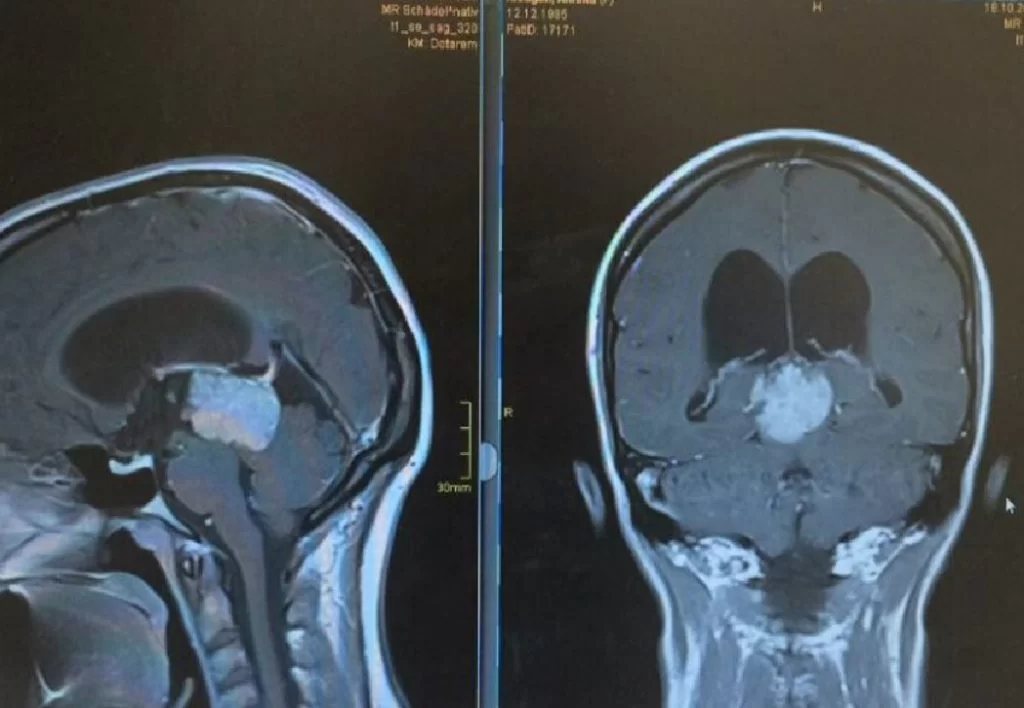

Ο απεικονιστικός έλεγχος με μαγνητική τομογραφία ανέδειξε ευμεγέθη όγκο στην περιοχή της επίφυσης (κωνάριο), καθώς επίσης και διάταση του κοιλιακού συστήματος (υδροκέφαλο)